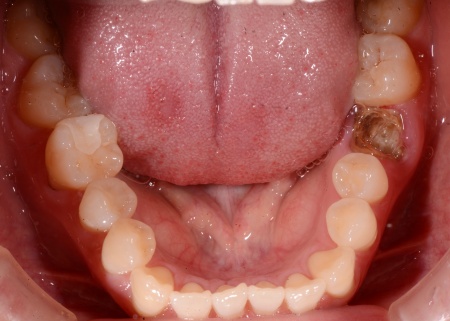

70代女性 虫歯が進行していた奥歯を抜いてインプラント治療で噛み合わせを回復した症例

拝見したところ、右下奥歯(第2大臼歯)の被せ物が外れ、奥歯でしっかりと噛めなくなっている状態でした。また、被せ物を支えていた歯の根っこには虫歯が認められます。

虫歯を削ってから詳しく検査をしたところ、虫歯が歯茎の中の深い部分まで進んでいたため、残念ながら歯を残すのは難しい状態です。